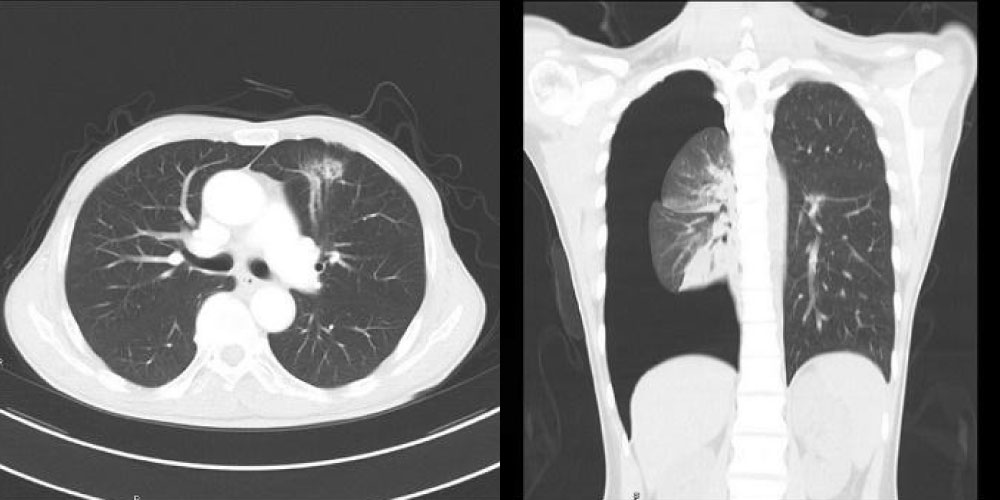

胸部領域

胸部CT検査は、肺や気管、気管支などの病変を見つけるために行なわれます。

最新型80列CT装置を導入により、短時間の息止めで撮影が可能です。

当院では最新鋭のマルチスライスCTを使用し、レントゲン写真では見つけにくい小さな病変も早期に発見することが可能になります。